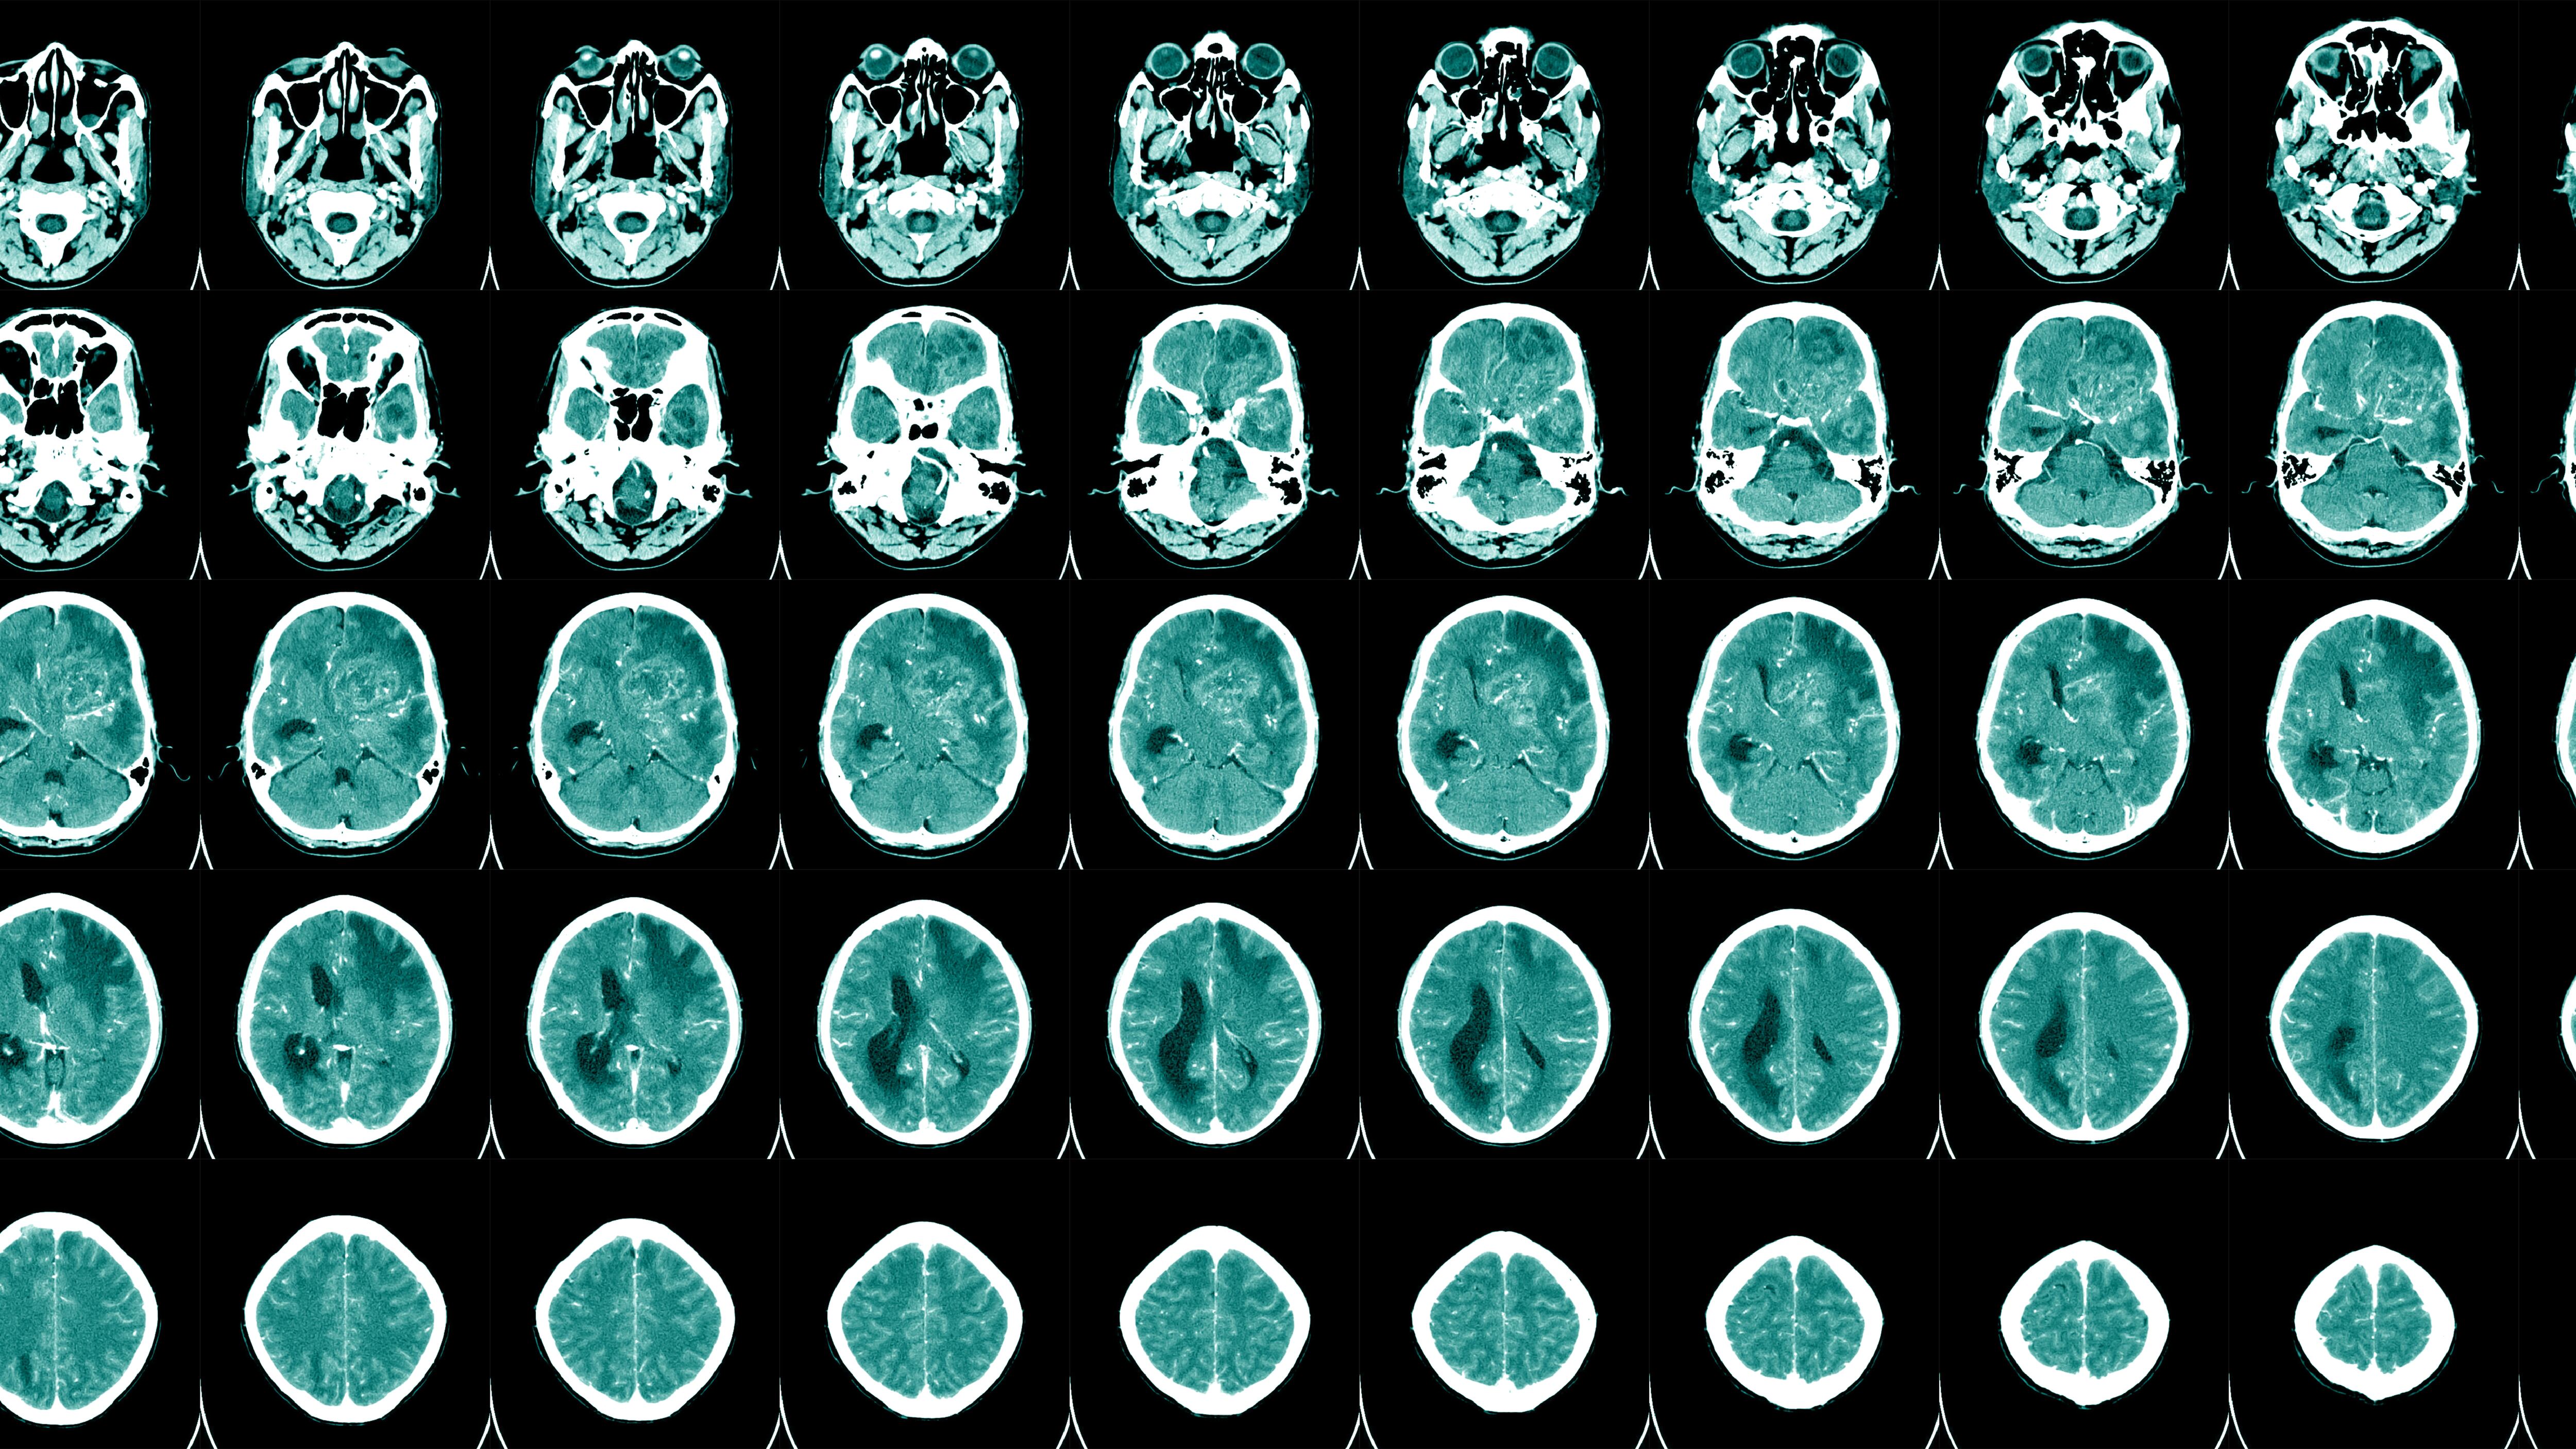

Aphasia is a disorder that results in loss of language, usually due to damage to the parts of the brain responsible for language.

According to the National Institute on Deafness and Other Communication Disorders, aphasia most commonly presents suddenly after an injury or stroke. Still, it can also develop slowly in connection with a brain tumor or progressive disease.